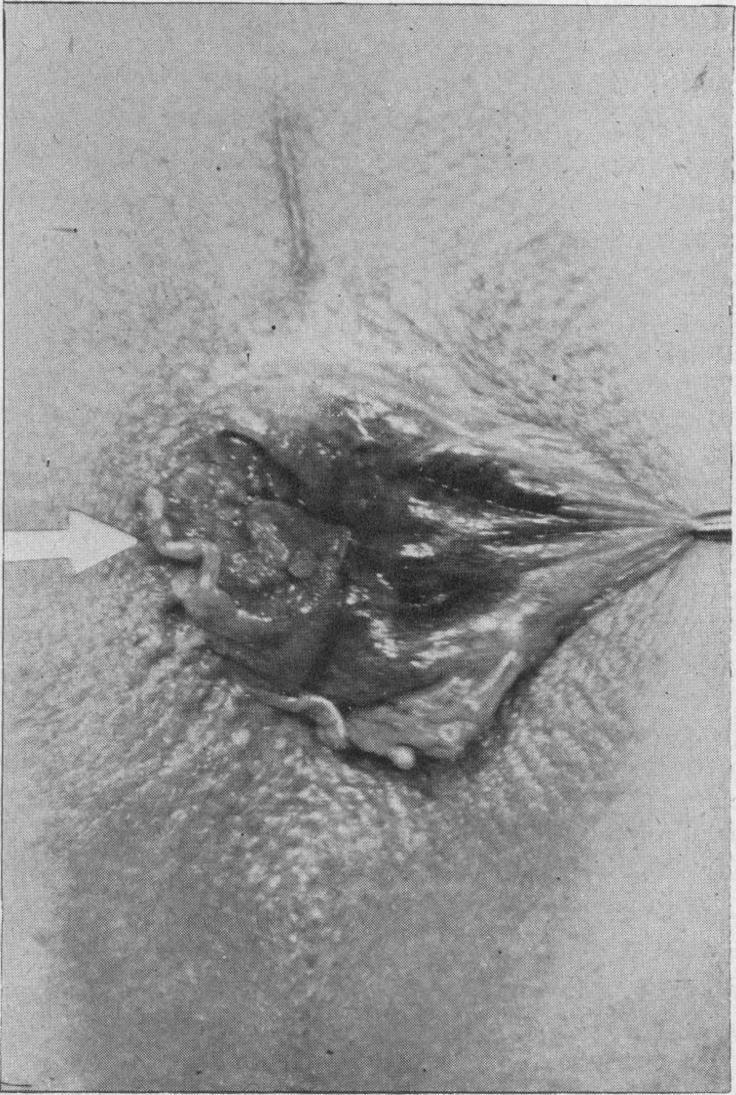

The analysis is of 55 cases admitted into St. Mark's Hospital from 1922 to 1940.The incidence was 3.35% of all cases of cancer of the rectum, anal canal and anus admitted during this period.Sex distribution-27 males and 28 females.The average age (61.7 years) is higher than that of columnar-cell carcinoma of the rectum (57.4 years).Histology.-The cases have been graded into three grades of malignancy-low grade, medium grade, and high grade.Low grade squamous carcinoma is twice as frequent in men as in women, and generally originates at the anal margin.Medium grade squamous carcinoma is equally distributed between men and women; it may arise at the anus or in the anal canal.High grade squamous carcinoma is much more common in the female sex and is almost entirely limited to the anal canal.Quadrant affected-about one-third of the anal margin growths and one-half of the anal canal growths were situated anteriorly.Differential diagnosis from simple papilloma, simple ulcer, chronic inflammation, tuberculous ulcer, tuberculide, primary chancre, amoebic ulcer, basal-cell carcinoma, columnar-cell carcinoma.Biopsy and grading essential before treatment is decided upon.The results of treatment in the three grades of malignancy are described. The best results were obtained in the early low-grade cases treated by interstitial radium needling. In the medium and high grades only three five-year survivals can be reported and these followed excision of the rectum. The management of the inguinal glands is discussed and the importance of a very close post-operative supervision emphasized.Squamous carcinoma of the anal canal may cause lymphatic metastases in the superior haemorrhoidal glands; there have been four such cases in this series. Diathermy perineal excision is indicated in these cases.